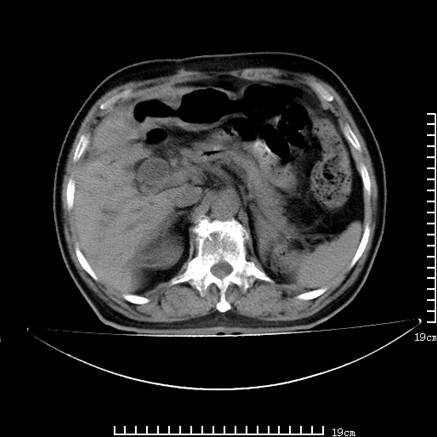

以下是引用lirenxiong在2008-7-19 22:01:00的发言:[br]胆总管结石并胆系感染,胆囊切除术后改变!左肾未见!左肾上腺增生肥大?请全腹扫描,增强!

以下是引用lirenxiong在2008-7-19 22:01:00的发言:[br]胆总管结石并胆系感染,胆囊切除术后改变!左肾未见!左肾上腺增生肥大?增强!